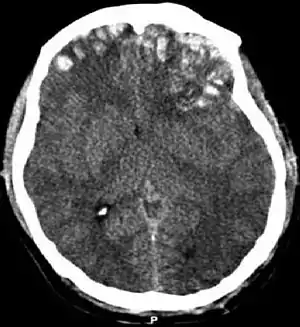

Movement disorders that may develop after TBI include tremor, ataxia (uncoordinated muscle movements), spasticity (muscle contractions are overactive), myoclonus (shock-like contractions of muscles), and loss of movement range and control (in particular with a loss of movement repertoire).[89][147] The risk of post-traumatic seizures increases with severity of trauma (image at right) and is particularly elevated with certain types of brain trauma such as cerebral contusions or hematomas.[138] People with early seizures, those occurring within a week of injury, have an increased risk of post-traumatic epilepsy (recurrent seizures occurring more than a week after the initial trauma).[148] People may lose or experience altered vision, hearing, or smell.[11]